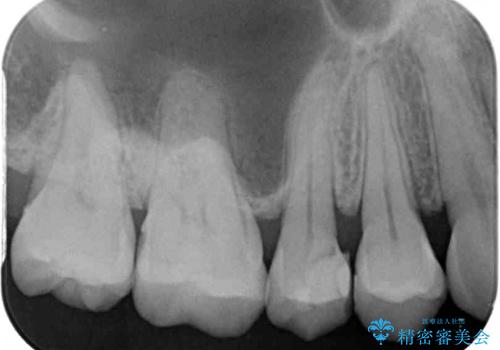

- 以前詰め物をした奥歯に物が頻繁に挟まるとのことで来院された患者様です。

充填物は形態が不正であり、歯肉付近にバリのように充填材料が飛び出していたため、歯肉が腫れやすい状態でした。

精密に治療を行うため、型取りを行った上でセラミックインレーによる修復治療を行うこととしました。